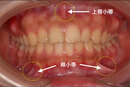

頬小帯(きょうしょうたい)

頬の粘膜から上下の小臼歯付近にかけて伸びるヒダ。咀嚼時に頬が歯に引き込まれすぎないようにする役割があります。

上唇小帯(じょうしんしょうたい)

上唇と前歯の歯茎をつなぐヒダ。上唇の動きや前歯の隙間(正中離開)に関係します。